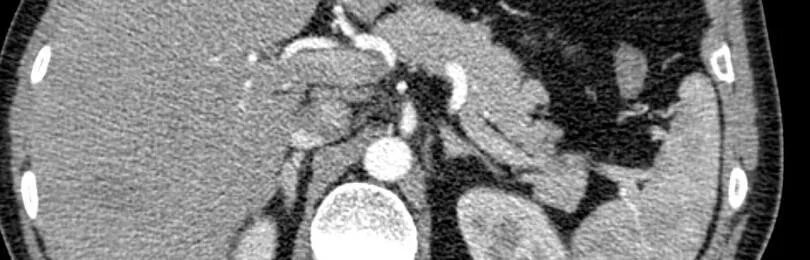

Гиподенсивное образование что это значит